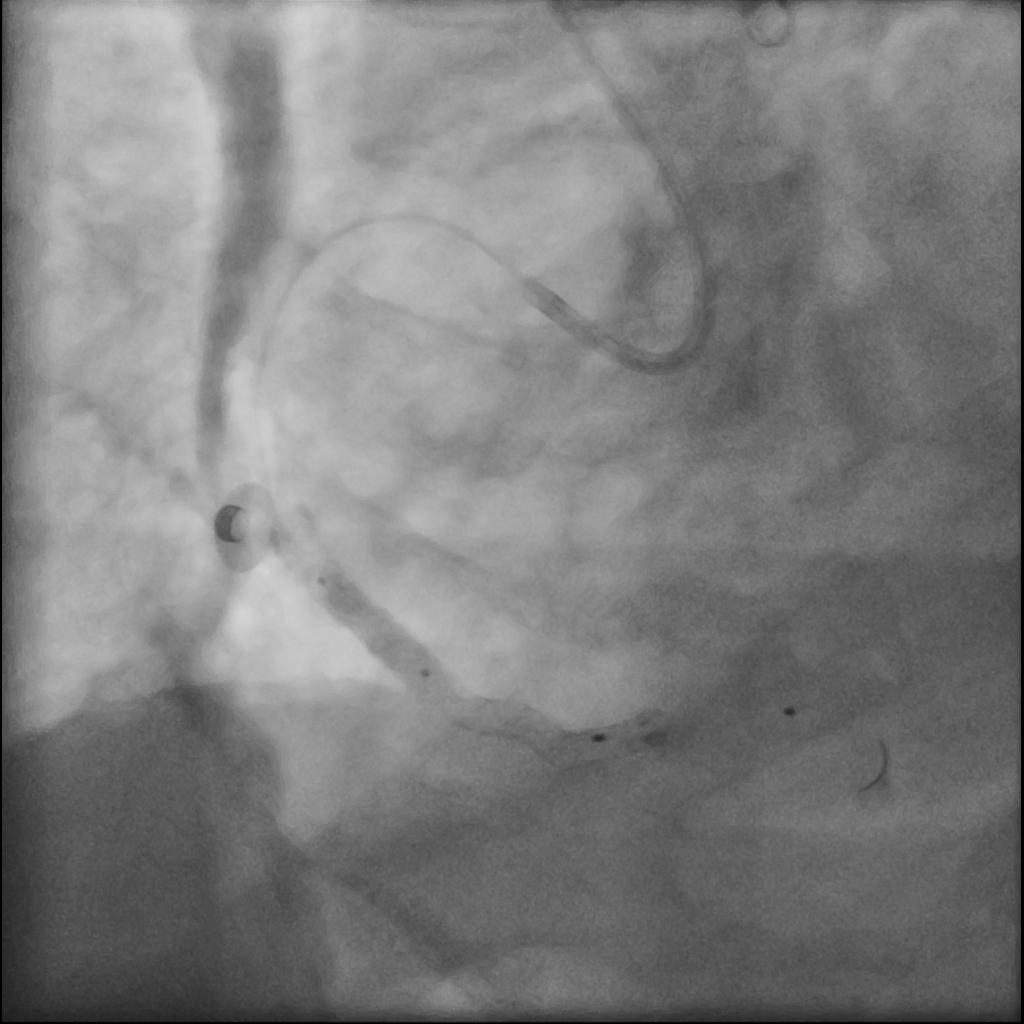

Using an AL1 guiding catheter, we navigated to the RCA-PDA. We performed balloon dilatation of the lesions in the RCA-M to RCA-D. IVUS with manual pullback revealed fibrous plaques with lipid pools and a glimpse of circumferential calcification in the RCA-M. We positioned the Spider FX embolic protection device with its filter basket in the RCA-D. Lesion preparation was done with a Euphora 3.5x30mm balloon. Stent deployment involved deep seating and using a guide extension catheter (GEC) to deploy an Ultimaster-Nagomi 3.5x44mm stent from RCA-M to RCA-D and another Ultimaster-Nagomi stent in the RCA-M. Notable underexpansion was observed in the middle part of the RCA-M stent . Post-dilatation was performed with an NC Accuforce 4.0x15mm balloon at 28 ATM. However, the RCA-M remained non-dilatable with persistent stent underexpansion. IVUS confirmed extensive circumferential calcification in the RCA-M. Despite multiple attempts using the GEC and balloon anchoring technique, we couldn't retrieve the Spider catheter's basket. We then used an intravascular lithotripsy balloon to deliver shockwaves to the proximal calcium ring, alternating with NC balloon inflations. Fortunately this inch-worm advance of the IVL achieved full stent expansion. Eventually, using an anchor balloon with GEC, we successfully retrieved the filter basket. The final angiography showed TIMI-3 flow in the RCA without any hemodynamic change throughout the procedure. A small emboli was found in the filter basket.